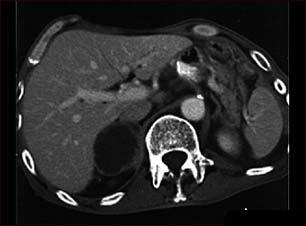

Boala Addison - insuficienta suprarenaliana lenta